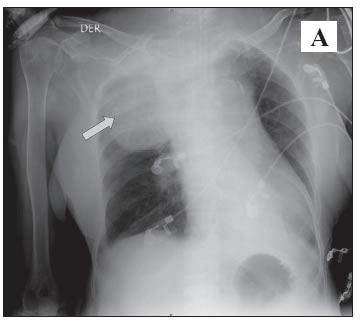

Mujer de 54 años quien ingresó con choque hipovolémico y séptico de origen abdominal requiriendo paso de catéter subclavio derecho para la administración de cristaloides e inotrópicos; la radiografía de tórax luego del procedimiento (Pánel A) mostró opacidad del hemitórax superior derecho con borde bien definido (Flecha), engrosamiento apical superior y mínima cantidad de líquido en el ángulo costofrénico ipsilateral, insinuando la presencia de hemotórax; por la condición clínica se realizó seguimiento clínico y radiológico. La paciente presentó mejoría, por lo que se retiró el catéter presentando nuevamente compromiso hemodinámico sugiriendo lesión vascular siendo necesario nueva radiografía de tórax (Pánel B) que mostró extensión de la lesión descrita (Flecha) y angioTAC (Pánel C) que evidenció hematoma en cuello y hemotórax derecho sin extravasación de líquido, aunque no se descartó lesión arterial (Flecha). La paciente presentó deterioro clínico y falleció antes de poder realizarse una intervención quirúrgica.